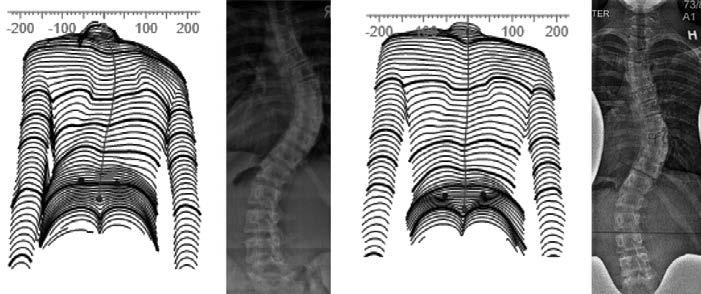

a b c d

Abbildung 158: Elfjährige mit idiopathischer Skoliose im Verlauf der Behandlung während des Hauptwachstumsschubs. Die Oberflächenvermessung und das Röntgenbild können verglichen werden. Nach zweijähriger Behandlung (c und d) erscheint der Rumpf des Mädchens bereits relativ symmetrisch und die Krümmung hat sich von 38 Grad Cobb (links) auf 19 Grad (rechts) verbessert.